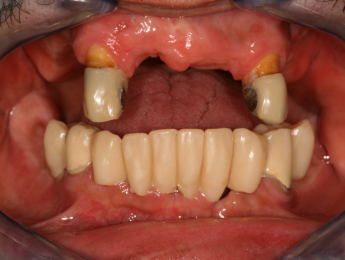

Implantátumok előtte-utána

Fogászati implantátumok előtte-utána

Implantátum beültetés előtt és után